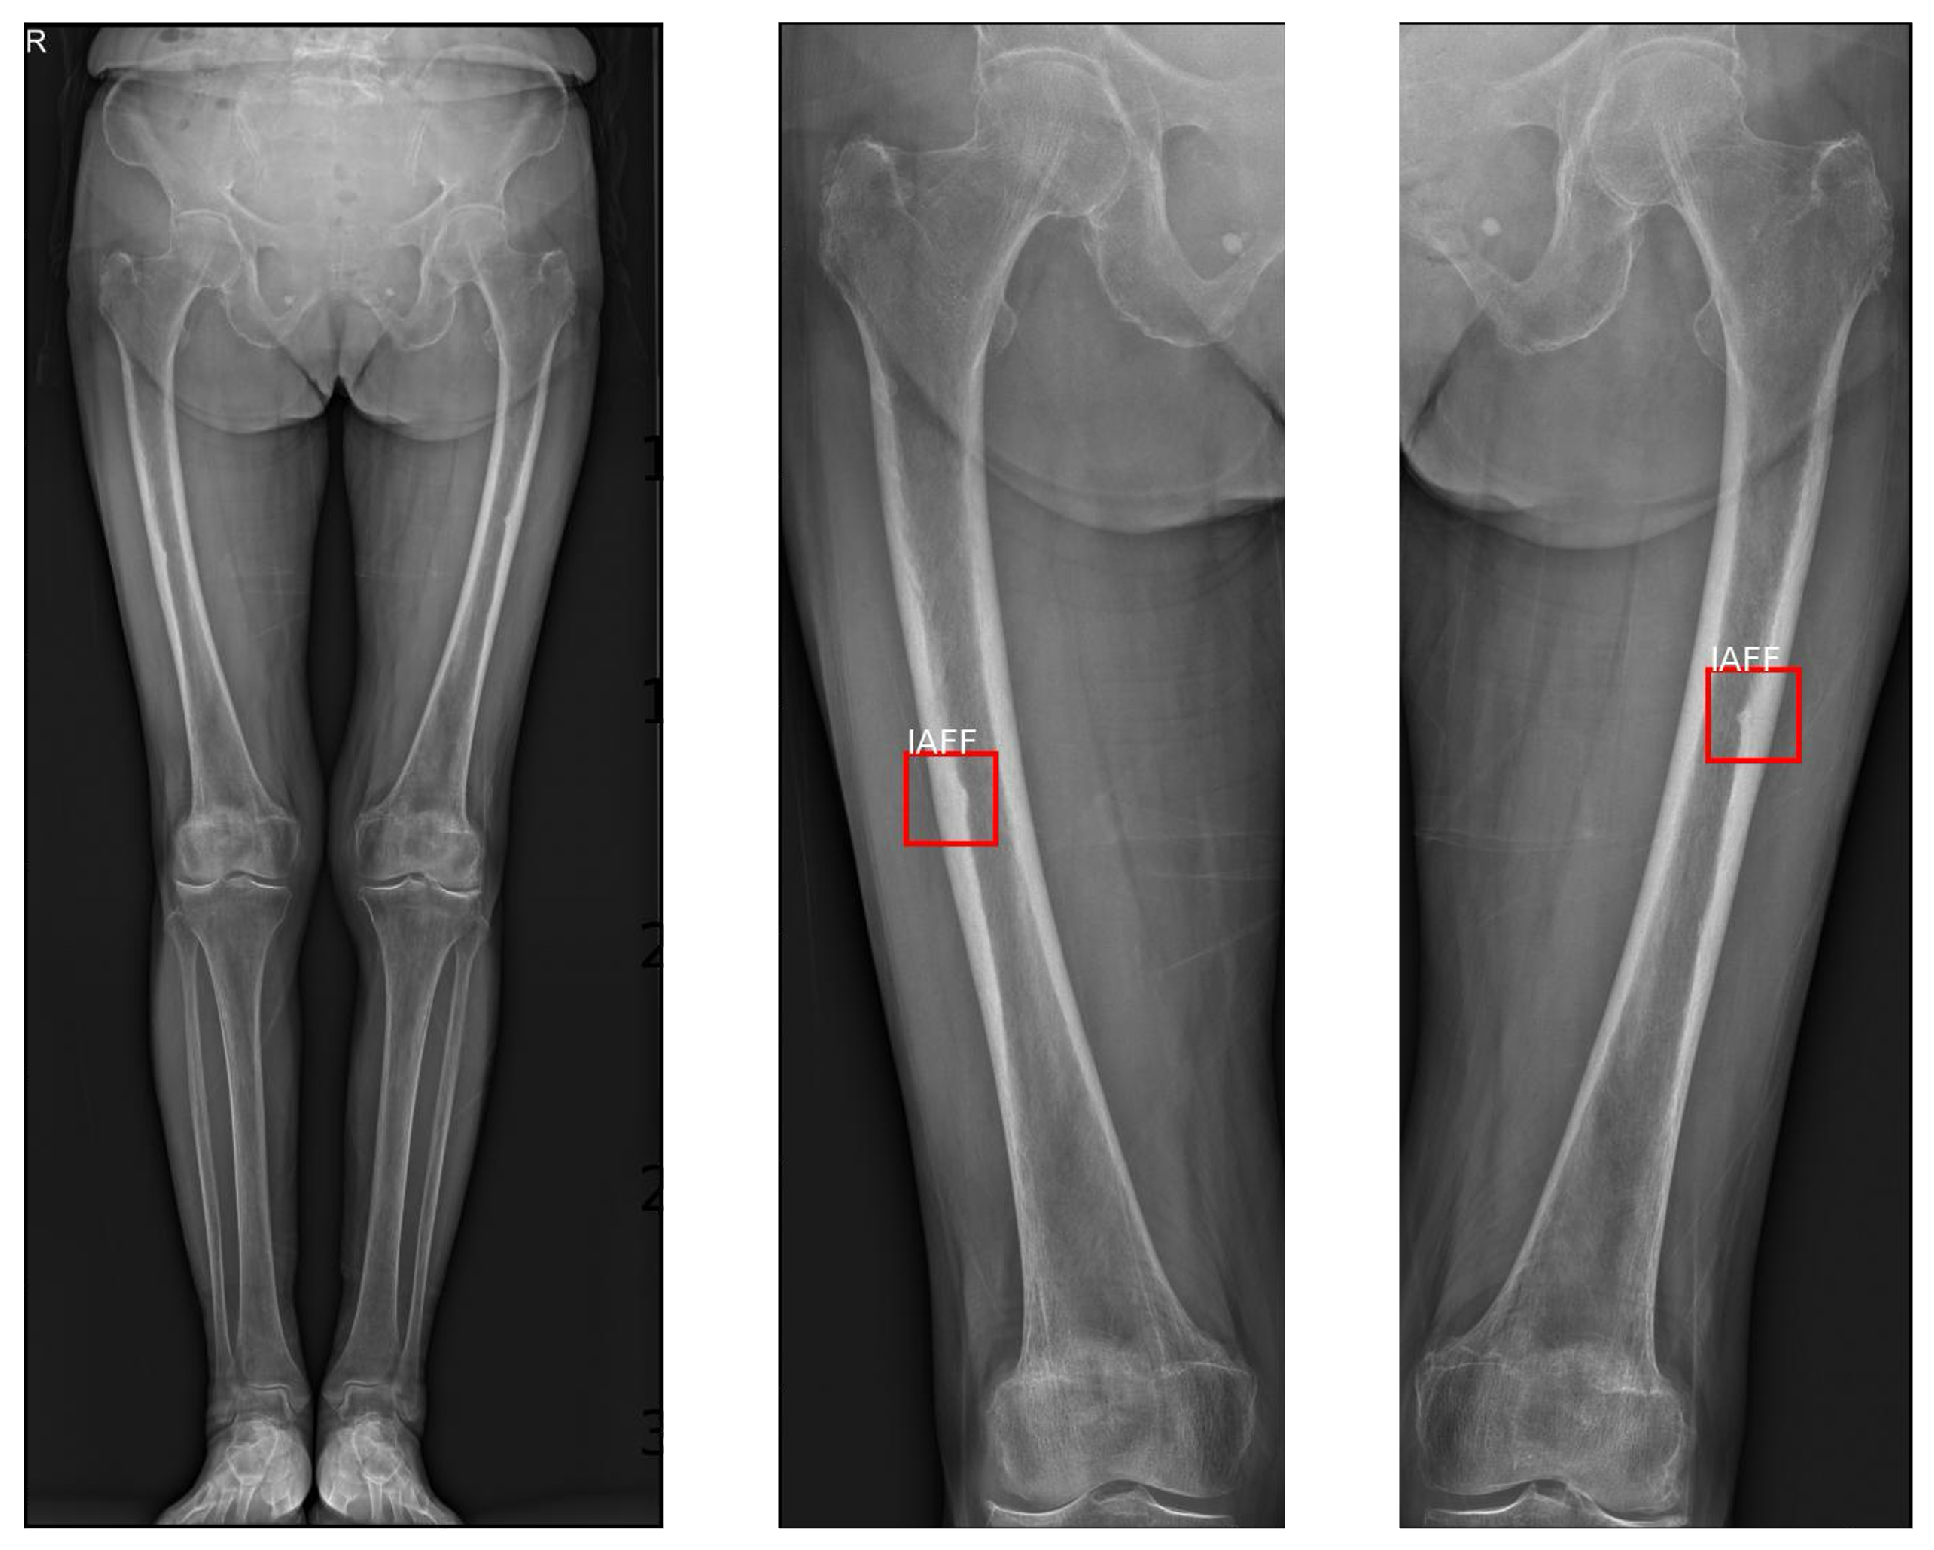

5.7. Visualization of Standing AP X-Ray